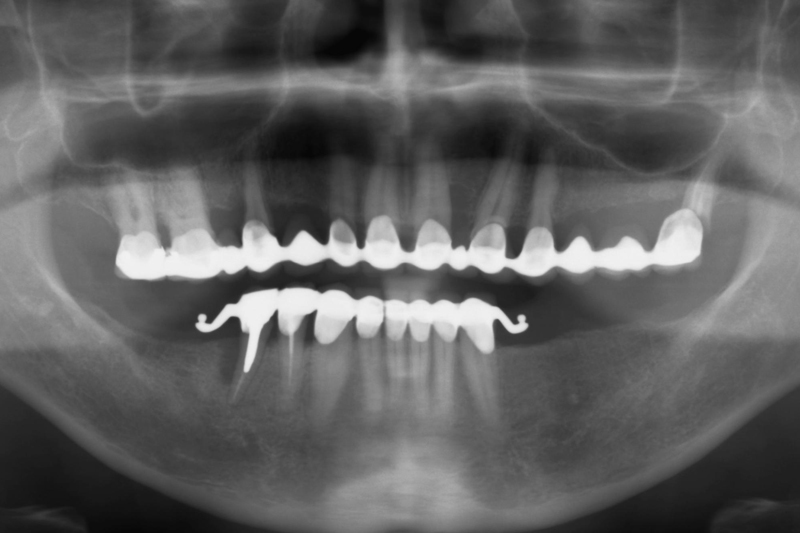

- Radiologiczny obraz kliniczny przed rozpoczęciem terapii